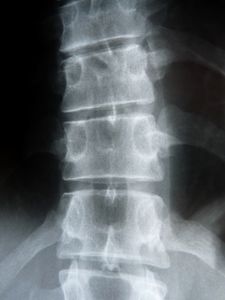

Rückenschmerzen: Paracetamol hilft nicht. Bild: pixelio.de, Dieter Schütz